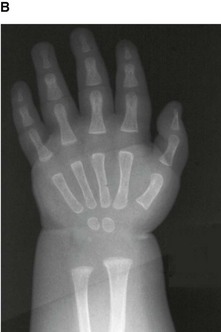

In the clinic Determination of skeletal age

Throughout life the bones develop in a predictable way to form the skeletally mature adult at the end of puberty. In western countries skeletal maturity tends to occur between the ages of 20 and 25 years. However, this may well vary according to geography and socioeconomic conditions. Skeletal maturity will also be determined by genetic factors and disease states.

Up until the age of skeletal maturity, bony growth and development follows a typically predictable ordered state, which can be measured through either ultrasound, plain radiographs, or MRI scanning. Typically, the nondominant (left hand) is radiographed and is compared to a series of standard radiographs. From these images the bone age can be determined (Fig. 1.13).

image image image image image

Fig. 1.13 A developmental series of radiographs showing the progressive ossification of carpal (wrist) bones from 3(A) to 10(E) years of age.

In certain disease states, such as malnutrition and hypothyroidism, bony maturity may be slow. If the skeletal bone age is significantly reduced from the patient’s true age, treatment may be required.

In the healthy individual the bone age accurately represents the true age of the patient. This is important in determining the true age of the subject. This may also have medicolegal importance.